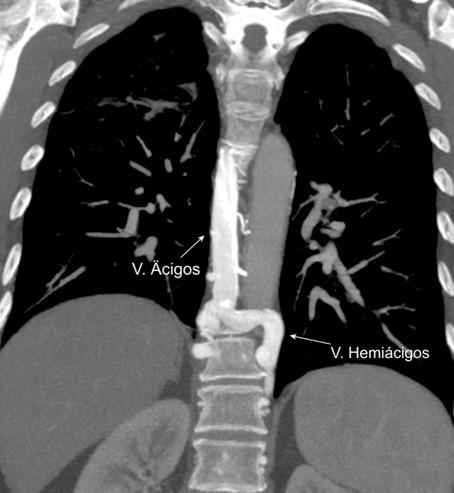

1. Obstrucción por encima de la V Ácigos. (La sangre llega al corazón a través de ella)

2. Obstrucción con participación de la V. Ácigos. (La sangre utiliza otras alternativas para llegar al corazón vía VCI).

Participación de la V. Ácigos como vía principal para llegar a la VCI.

Contiene: Grasa. Aorta y ramas

Venas ácigos y hemiácigos